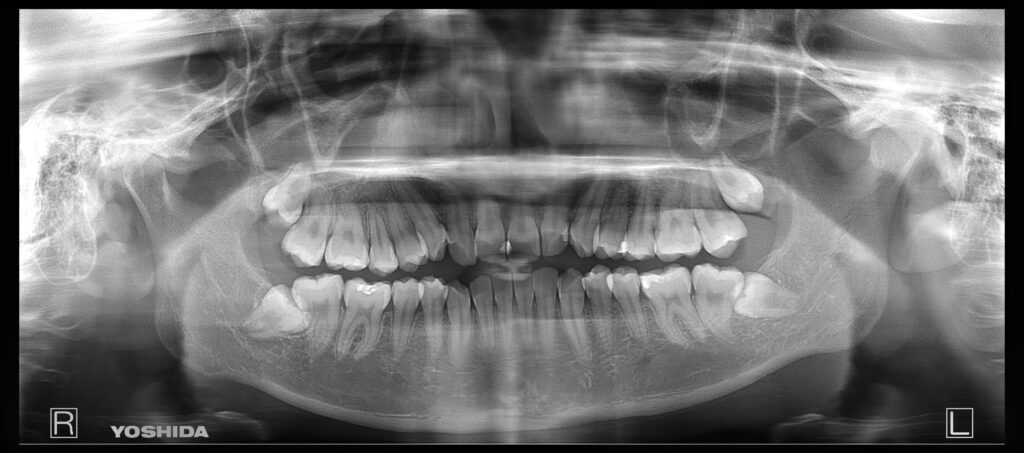

①親知らず抜歯前